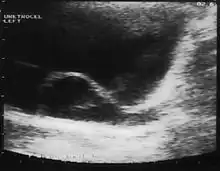

A ureterocele is a congenital abnormality found in the ureter. In this condition the distal ureter balloons at its opening into the bladder, forming a sac-like pouch. It is most often associated with a duplicated collection system, where two ureters drain their respective kidney instead of one. Simple ureterocele, where the condition involves only a single ureter, represents only twenty percent of cases.

Since the advent of the ultrasound, most ureteroceles are diagnosed prenatally. The pediatric and adult conditions are often found incidentally, i.e., through diagnostic imaging performed for unrelated reasons.